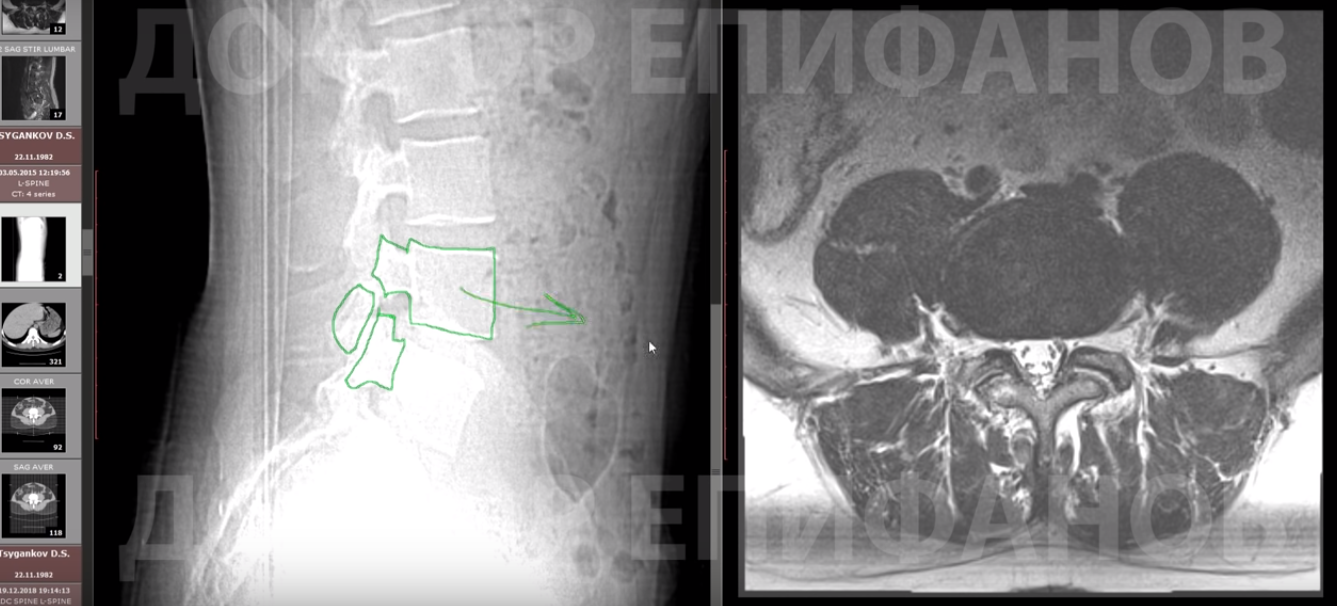

Обратите внимание, у пациента белые межпозвоночные диски — это признак того, что позвоночник хорошо питается. Прекрасный изгиб. Если бы не смещение, то пациент был здоров.

Есть грыжевое выпячивание, но на фоне листеза грыжи лечатся плохо и не уменьшаются. Даже мы редко берём такие на терапию.

Смотрим межпозвонковые отверстия. Одно нормальное: нерв, никаких протрузий и грыж. Второе выглядит немного изменённым, нерв нашёл себе место, но нет протрузии. Конечно, дополнительная составляющая может давать болевой синдром.

Позвонок нестабилен, поэтому он стремится уехать вперёд. На фоне нестабильности таких позвонков начинают болеть еще и суставы. На снимках заметна гипертрофия суставных поверхностей, они могут болеть.